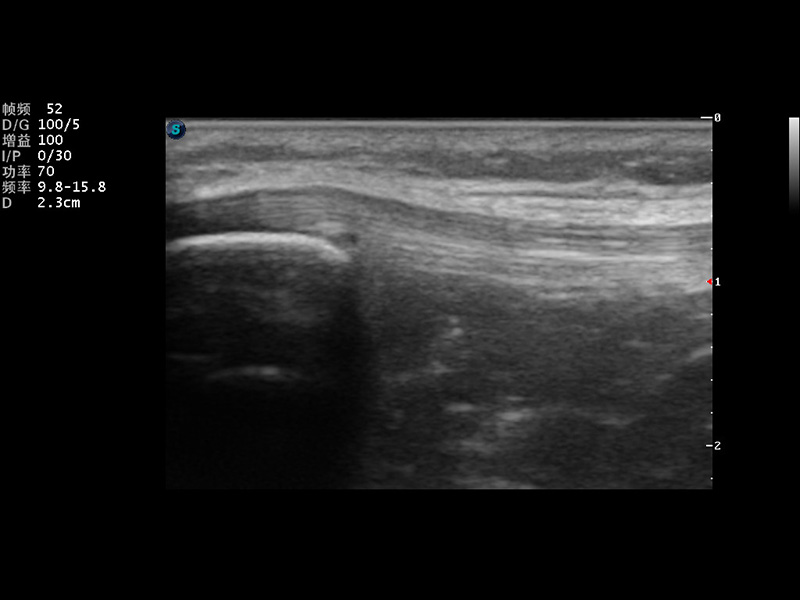

S9便携式彩色多普勒超声诊断仪是哈哈体育官网研发的高端便携彩超设备,外观设计新颖、产品性能卓越。S9在便携超声领域采用了突破传统的触摸屏交互设计,并以先进的软件硬件技术和设计理念,为您带来清晰的图像质量、稳定的工作性能和便捷的操作体验。